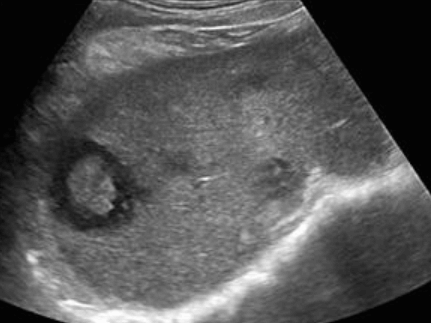

- bull's eys sign (종양 변연에 중심부가 고에코이고 경계부가 저에코인 두꺼운 띠가 보인다)

- cluster sign (종양이 융합하여 분엽모양을 이루어 마치 포도송이 모양을 나타낸다)

US finding

- 동일한 크기의 다발성 종괴가 나타난다.

- 고에코의 다발성 종괴: 대장암이 많으나 위암도 비교적 흔하다.

- 저에코의 다발성 종괴: 유방암, 폐암등에서 나타난다.

- 석회화나 내부 낭성 변성은 전이성 간종양을 시사하는 소견이다.